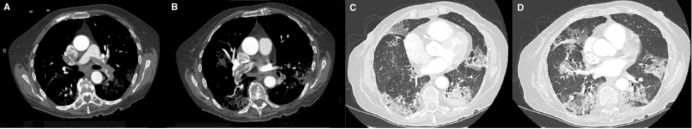

2020年Eur Heart J杂志发表了一个病例[1],为75岁女性COVID-19患者,因发热10天、新发呼吸困难入院,无明确VTE危险因素。WBC 11.36×109/L(↑),CRP 180 mg/L(↑),cTnI 3240.4 ng/ml(↑),D-dimer 21 μg/ml(↑);吸氧状态下动脉血气分析示PaO2 78.0 mmHg,PaCO2 25.1 mmHg,SaO2 95.6%。超声心动图示右室扩大,右室收缩功能严重减低,估测肺动脉平均压60 mmHg;下肢静脉超声未见血栓;CTPA示双肺动脉分支多发肺栓塞。该病例提示我们:严重的COVID-19肺炎可能是急性VTE的危险因素。

图源:Eur Heart J, 2020, 41(19):1858.